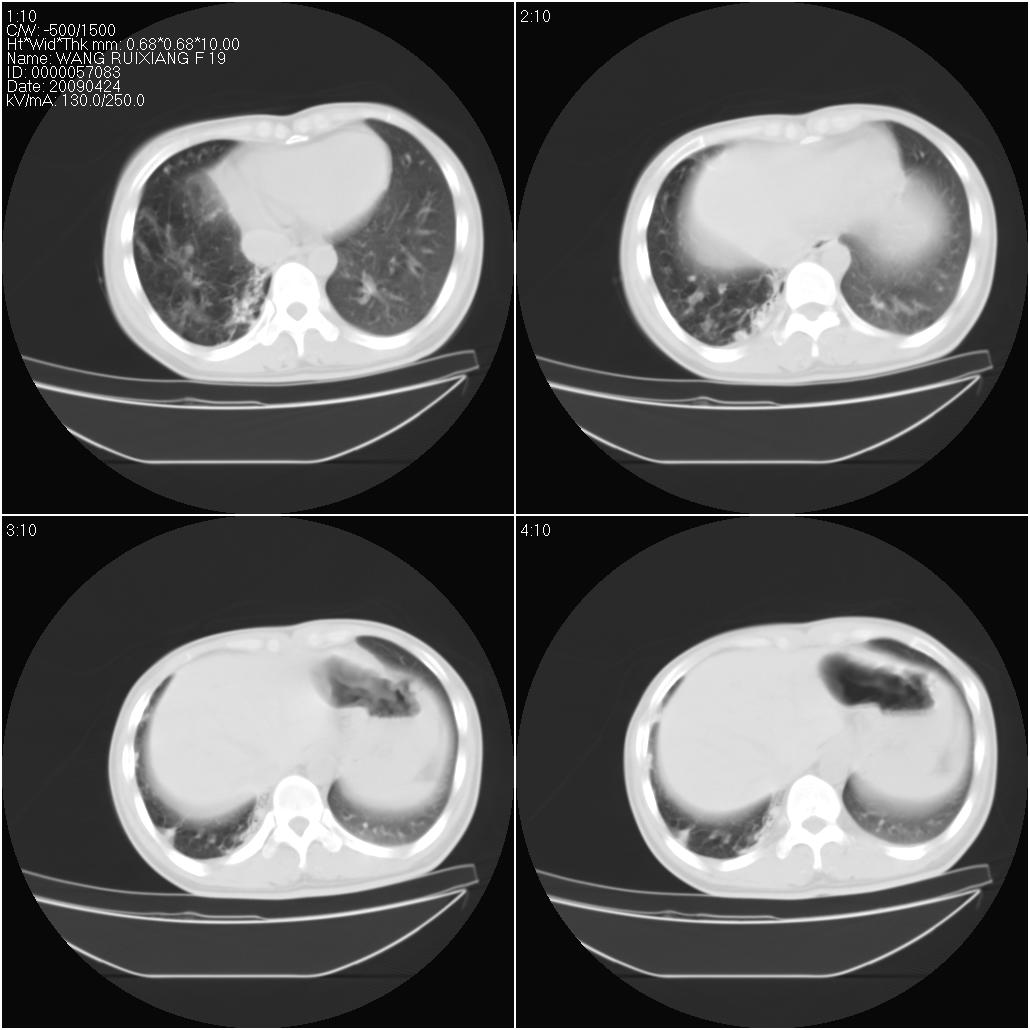

片子上的年龄为19岁,是操作错误。该患者于去年5月份曾做平片和ct扫描,和这一次的ct检查没有明显变化。当时诊断为肺结核,进行抗痨治疗至今,但没有改善。呼吸功能试验为混合型呼吸困难。除此之外,该患者没有其他方面没有的临床症状和体征

两肺见斑点片状阴影,部分病灶密度较高,右下肺见小囊状及柱状蜂窝状阴形,考虑为两肺结核以阵旧性为主,右下肺支扩。

1)两肺继发性肺结核(以增殖病灶为主)。2)两肺下叶支气管扩张。

1)两肺继发性肺结核(以增殖病灶为主)。

2)两肺下叶支气管扩张。